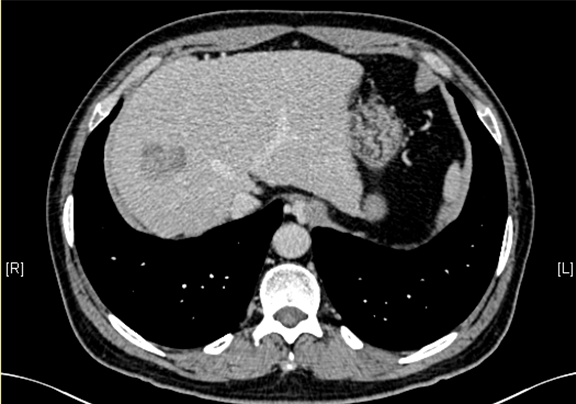

术前CT检查:

静脉期

下腹部增强CT示:肝右叶恶性肿瘤可能性大;肝内多发小囊肿;肝硬化,食管胃底静脉曲张可能性大;脾脏囊肿可能性大。